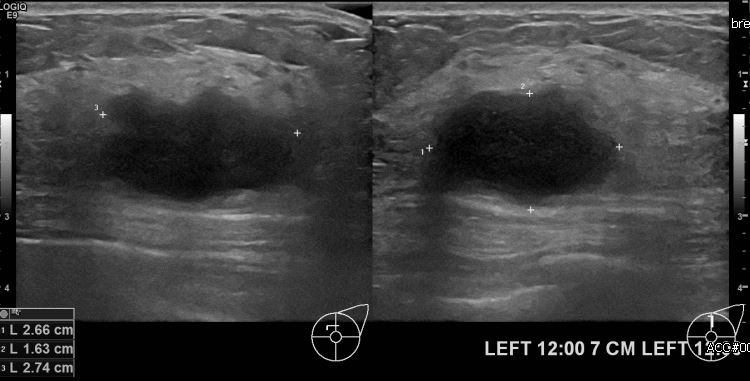

좌측유방에 만져지는 멍울로 내원하신 50대 여성분으로 좌측 12시 방향에서

7cm 떨어진 거리의 멍울 조직검사 시행하여 좌측 침윤성 유관암 진단되었습니다.